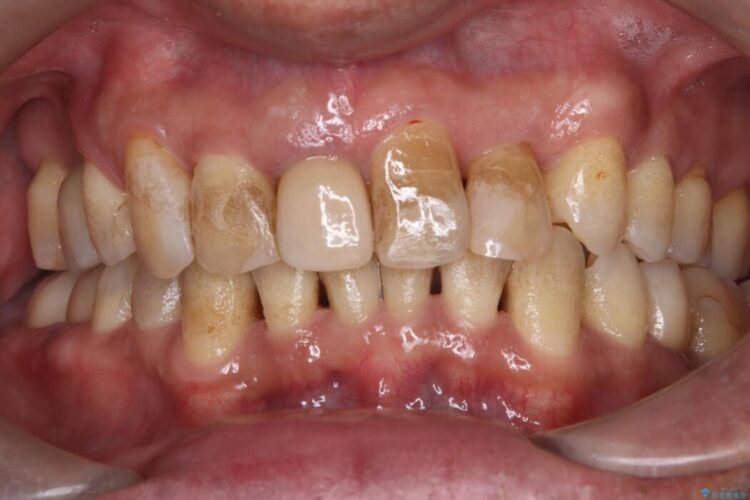

長期的な安定性を重視したセラミック治療

歯と歯の間に虫歯があった患者様です。

治療期間(治療回数):1ヶ月(2~5回) | 概算治療費:13.2万円(税込)(仮歯:10,000円+オールセラミッククラウン 3年保証110,000円)